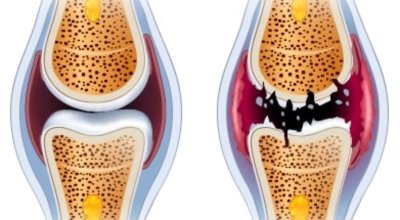

콘드로이틴을 말하는것으로 골 관절염의 관절 질환 치료에 글루코사민과 동반해 사용되는 물질의 성분입니다. 콘드로이친은 탄수화물의 한 종류로 연골 탄성섬유의 중요한 주물질입니다. 상어의 연골에 들어 있는 물질으로 신체의 관절, 연골, 피부에 적은 양으로 존재하는 물질이라고 알려져 있습니다. 콘드로이친은 연골의 파괴를 예방하고 새 연골 생성을 활성화하는데 많은 도움되는 것으로 알려져 있습니다.

글루코사민에 대조해 원료가 100배가량 비싼 고가의 원료인것으로 알려져 있답니다. 관절염 이유가 되는 것으로는 관절 연골이 닳아 없어지기 때문인데 퇴행성 질환이라고 하는 이유가 연골이 더 이상 생성되기 어렵기 때문이죠. 특히 콘드로이친이라 하는 성분이 나이가 들면서 길이가 짧아지고, 크기가 줄어들기 때문에 연골 구조가 변화되어 가면서 무릎뼈의 간격이 좁아져 통증을 유발하는 원인이 되는데 이 경우에 콘드로이친 효능을 바라볼 수 있답니다.

콘드로이친 효능 중 가장 대표적인 것이 연골세포를 보존하는 역할이라고 합니다. 콘드로이친에는 연골세포의 분해를 억제시켜 연골세포를 보호해주며 유지시켜주는 기능이 있습니다. 연골은 노화가 진행될수록, 나이가 들 수록 점점 그 크기가 떨어지거나 끊어질 수 있지만 이 때에 콘드로이친이 그 스펀지와 같은 역할을 하여 연골 속 수분을 잡아주어 부드럽고 유연하게 유지할 수 있게 도와준다고 알려져 있답니다.

그 이유는, 노화가 진행되는 중장년층에게서 콘드로이친 수치가 저하되는걸 볼 수 있습니다. 이는 곧 연골의 뼈와 뼈 사이 완충효과 및 보호기능 약화로 이어지는데 이를 보충하면 관절염을 해결하는데 도움을 줍니다. 그리고 콘드로이친은 관절세포를 재생시키는데 도움이 되고 외부 충격을 흡수, 완화하는데에도 최고의 효과가 있어요.